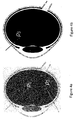

- FIG. 2a The two-dimensional projection in the x-y plane of the three-dimensional surface defined by the geometry equation is shown in Figure 2a .

- Figure 2b shows the canonical two-dimensional limacon.

- the geometry equation defines a generalized three-dimensional limacon, which has an additional parameter for defining the shape, p 3 . In virtue thereof, a realistic representation of the vitreous body can be achieved.

- the values for the geometry parameters p 1 , p 2 , p 3 and m x are obtained by fitting eye measurement data as shown in Figure 2c .

- the eye measurement data about the shape of the outer surface of the vitreous body are obtained by means of ultrasound imaging technique.

- the eye measurement data comprise a plurality of coordinates for points on the outer surface of the vitreous body.

- the data points shown in Figure 2c are the two-dimensional projections of the eye measurement data.

- the formula for an average vitreous body can be determined.

- Figure 2d shows different models for the shape of the vitreous body overlapped with the eye measurement data.

- a circle fit shows three fits shown: a circle fit, a conventional limacon fit and a generalized limacon fit according to the geometry equation above. It can be seen that the generalized limacon fit can best describe the actual shape of the vitreous body as measured.